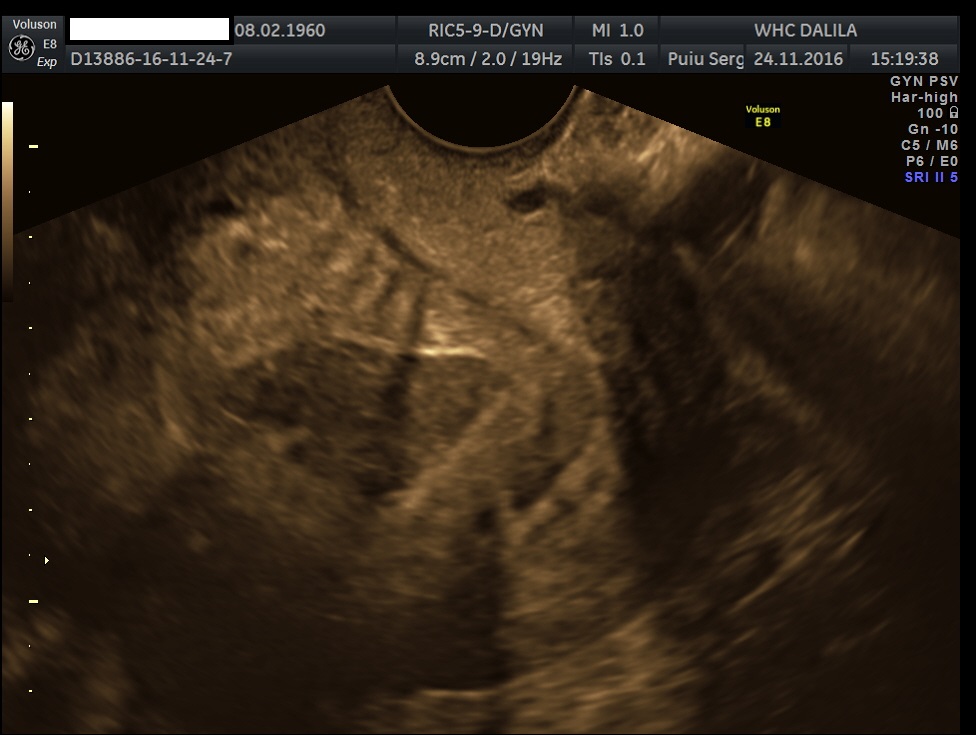

Transvaginal and transabdominal ultrasound scans were performed, which has shown the enlarged uterus with indistinct borders on the left side and a complex mass in left lower abdominal quadrant. A large irregular thick-walled, ill-defined multiloculated cystic/solid lesion with complex fluid collections and peripheral flow on color Doppler were seen. The anatomic distinction between the ovary and the fallopian tube could no longer be identified (Fig. 1). A tubo-ovarian abscess (TOA) was presumed. Endovaginal sonogram showed a dilated uterine cavity and cervical canal, filled with heterogeneous, complex fluid and echogenic masses (Fig. 2a-c). An intrauterine contraceptive was detected. A cavity within myometrium with low-level internal echoes fluid also was revealed (Fig. 2c). This complex adnexal mass was adherent to uterus and a communication between TOA and the cavity within myometrium with fluid-debris level fluid was detected (Fig. 3a-b). This finding presumed a perforation of the TOA into uterus, due to myometrium necrosis, and spontaneous drainages into uterine cavity through myometrium. Increased echogenicity of the pelvic fat and a small amount of free fluid in cul-de sac also were seen. Fluid movements through fistula canal between TOA and uterine cavity were clearly seen when a gently pressure by ultrasound probe was applied (Video 1).

Figures 2a-c. Endovaginal sonograms. Dilated uterine cavity and cervical canal, filled with heterogeneous, complex fluid and masses. An intrauterine contraceptive device also can be easily seen. Note the cavity within myometrium with low level internal echoes fluid and a fluid-fluid level on figure 2c.